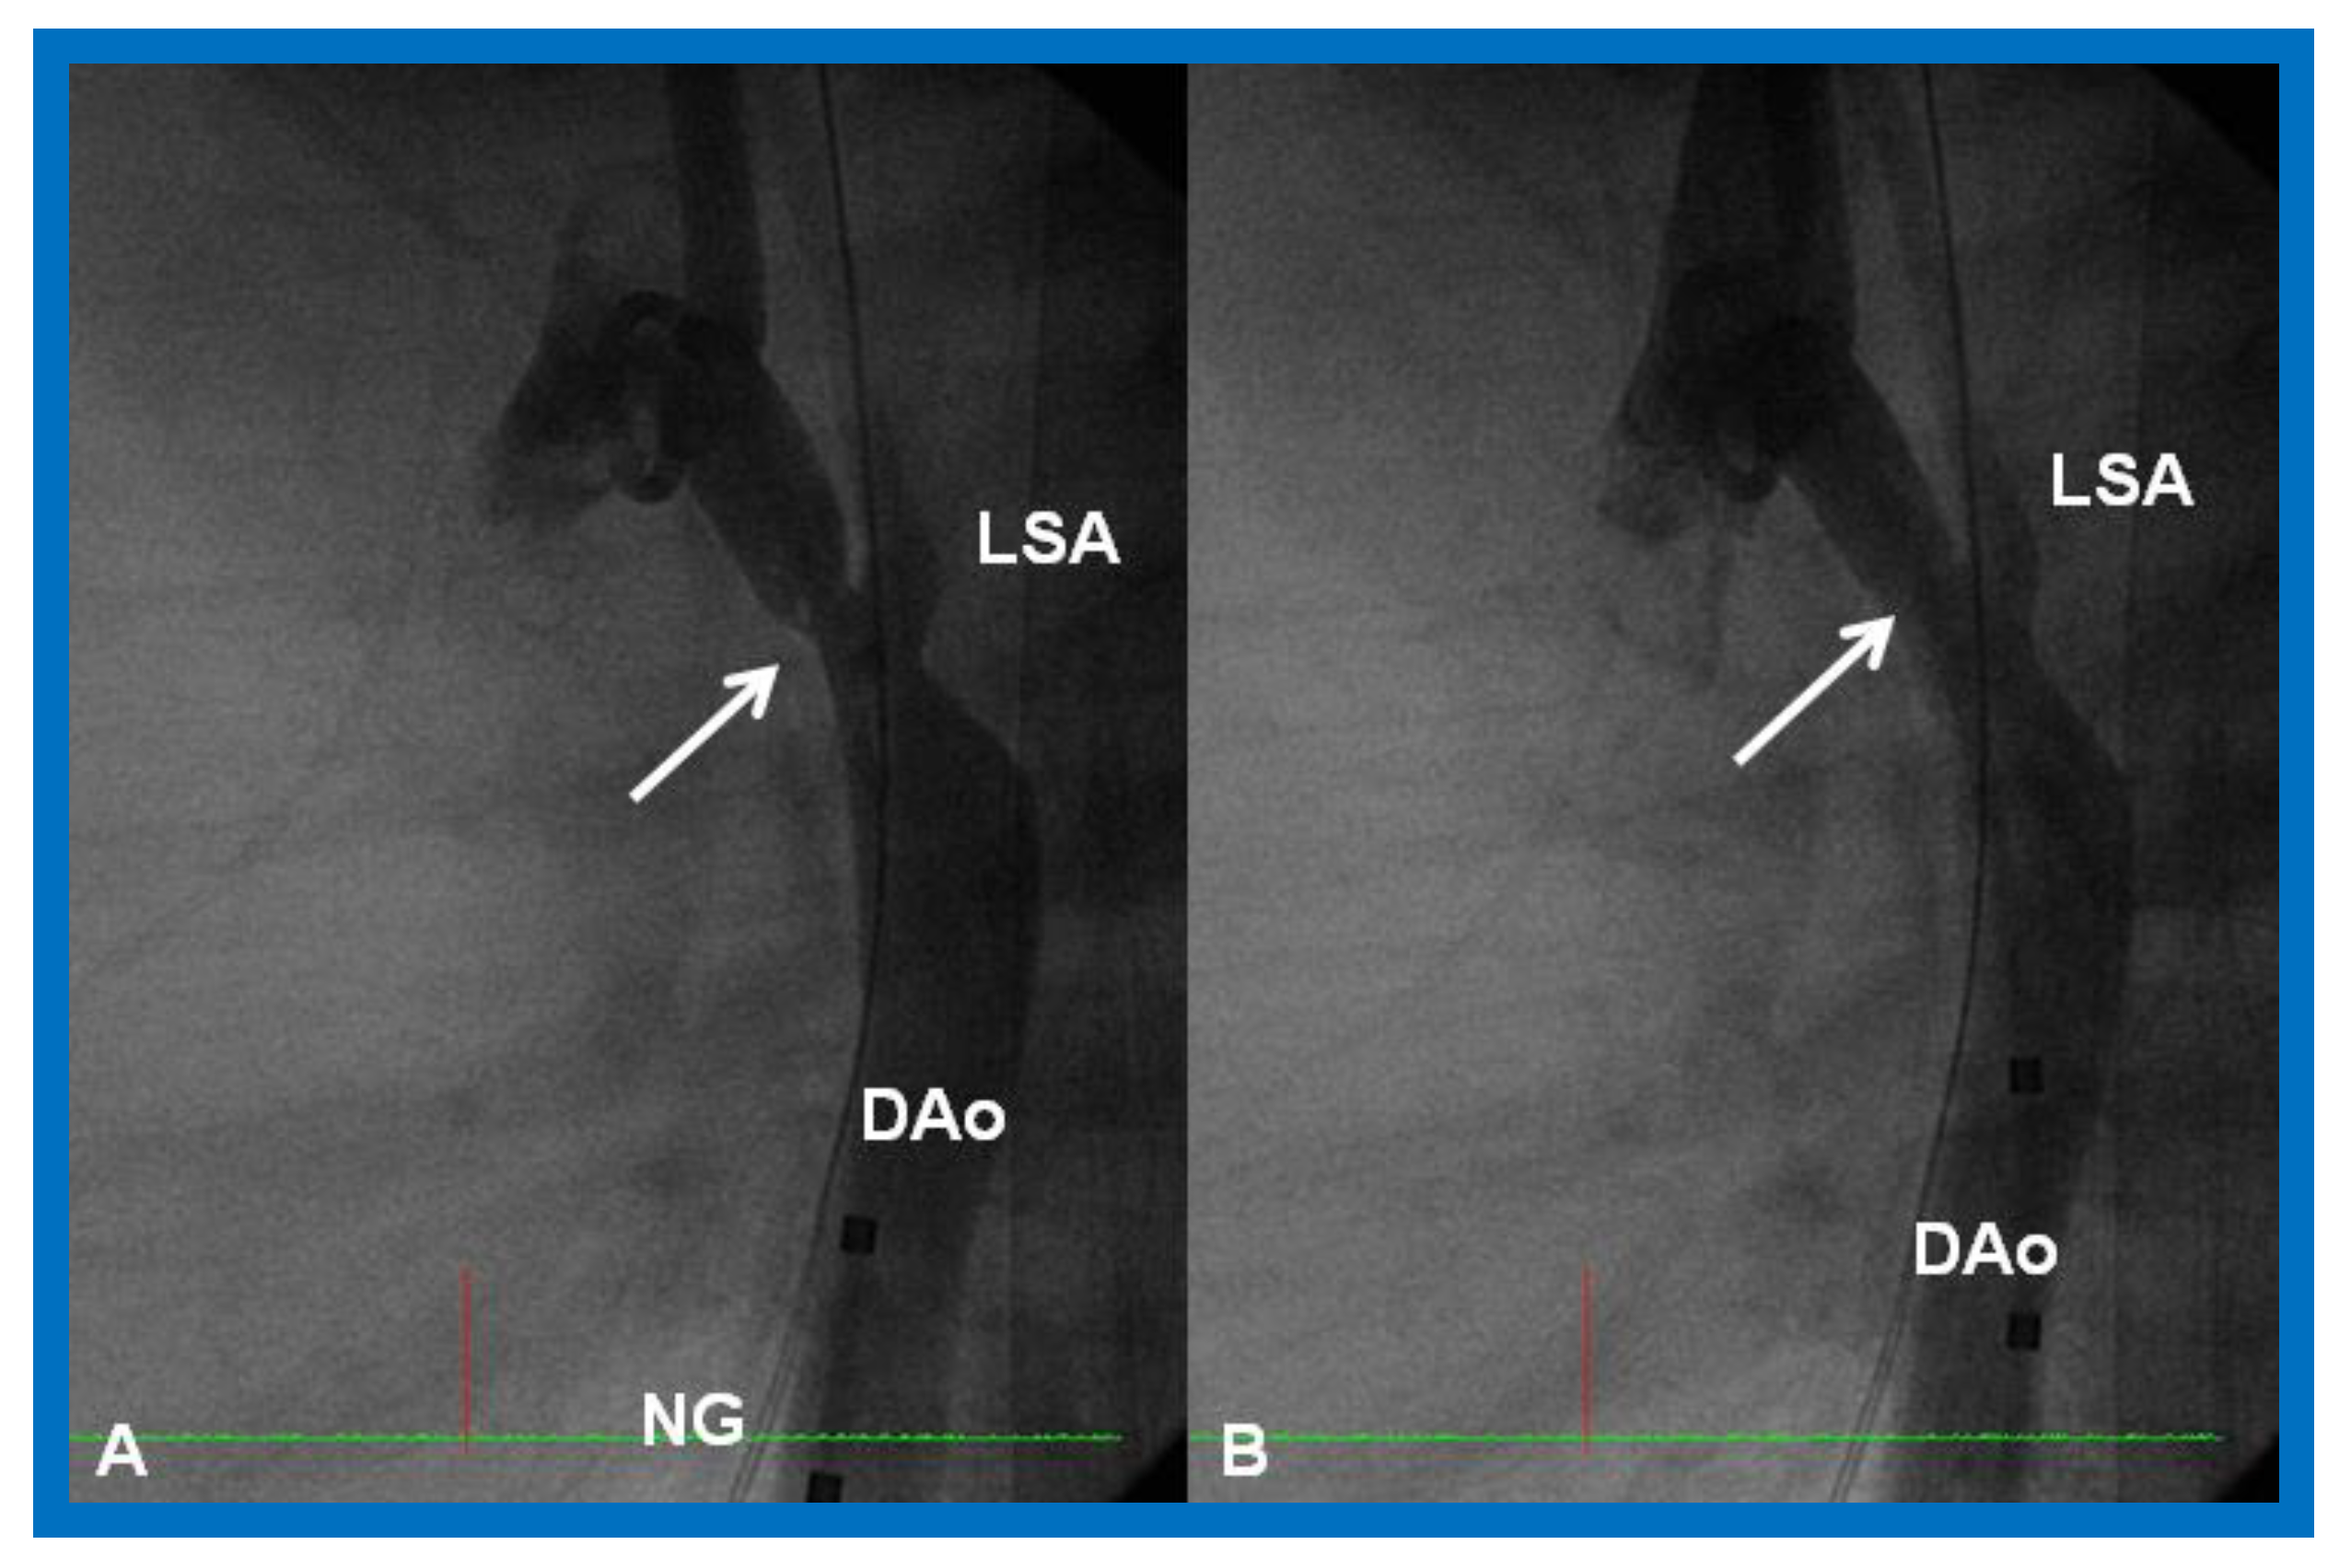

Figure 25.

Cineangiographic frames from aortic arch angiograms in straight lateral projection showing a post-surgical recoarcted aortic segment (arrow) priot to balloon angioplasty (A) which improved (arrow) following balloon dilatation (B), in a neonate who developed recoarctation at three weeks of age after neonatal surgical repair of coarctation. DAo, descending aorta; LSA, left subclavian artery; NG, nasogastric tube. Reproduced from Reference [58].